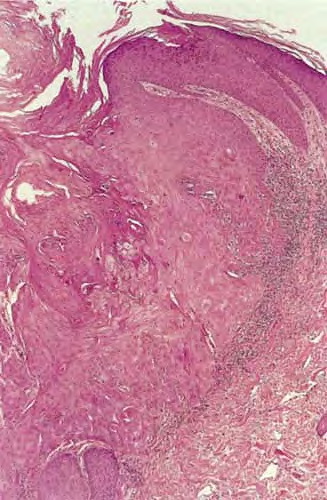

The histopathologic features of keratoacanthoma depend on the stage of evolution of the tumor. In early, proliferative lesions, the epithelium is markedly hyperplastic, and the central keratotic plug is not as pronounced as in fully developed lesions. The lesion has an overall symmetric aspect . Although atypical cells do not represent the majority of the cells in typical keratoacanthoma, there may be atypical keratinocytes and mitoses, especially at the lower margin of the tumor. Nests of epithelial cells may detach from the main tumor mass and be found in the superficial reticular dermis. Fully developed, mature lesions are characterized by a large central core of keratin surrounded by a well-differentiated proliferation of squamous epithelium that in some cases may resemble squamous cell carcinoma . The epidermis at both sides of the central core extends over the keratotic area in a fashion that has been described as “lipping” or “buttressing,” giving a distinct crateriform appearance to the lesion. Nests and strands of keratinocytes may be found apart from the main bulk of the tumor but usually do not extend lower than the level of sweat glands .